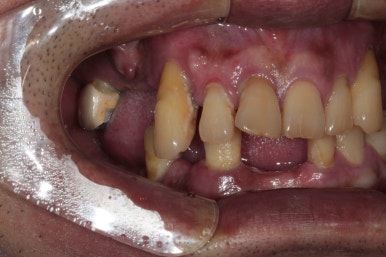

그나마 큰 어금니가 한 개 남은 오른쪽 위 구강 내 사진입니다.

딱 보시면 아시다시피, 만성치주염(풍치)를 심하게 앓고나서 치아를 빼면.. 남는 잇몸뼈가 별로 없습니다. 다 위축되서.. 임플란트 심기 곤란한 상황이 많이 생기죠.

그래서 더더욱이 치주염 치료를 위해 정기검진을 챙기셔야 하는 이유랍니다.

아래 앞니도 상당히 좁아져버린 잇몸뼈의 모양을 관찰하실 수 있을거에요.

이런 부위는 임플란트를 심어내기에도 어려워져 버린답니다.

심해진 만성치주염으로 인해 위 앞니들은 제 자리를 잃어버렸습니다.

치아 사이 간격이 커지기도 하고, 정출되는 등 병적 치아이동 (pathologic migration)을 겪게 되지요.